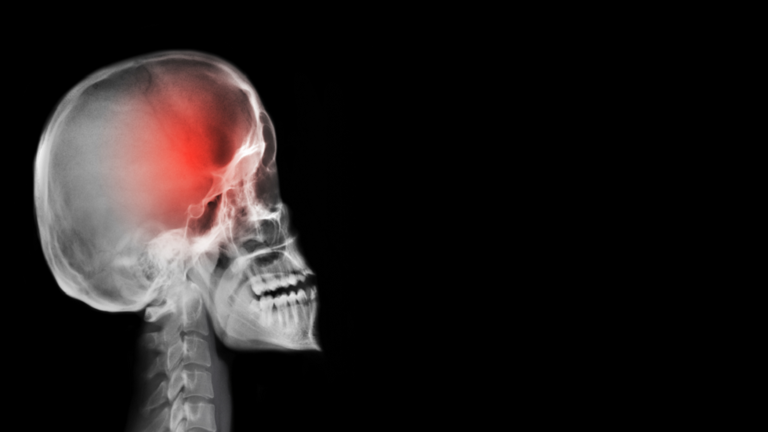

خطير .. اذا ظهرت عليك احد هذه الاعراض الخمس فهي تدل أن الصداع علامة على وجود ورم في المخ!